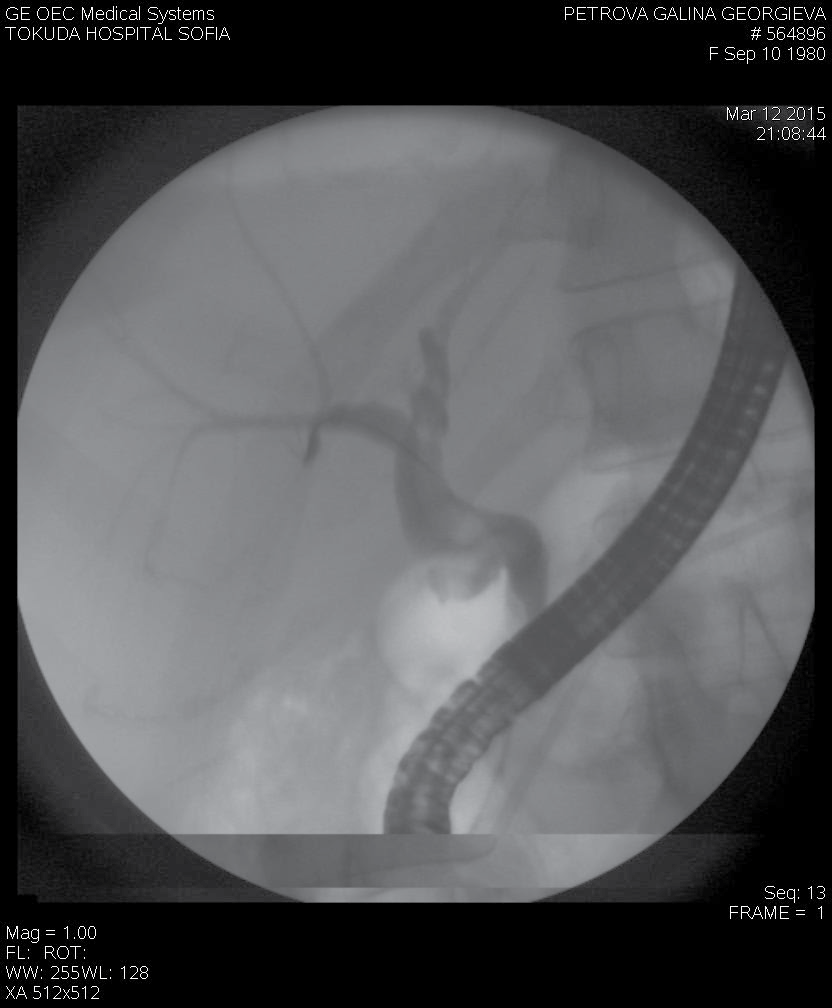

The examination of the papilla of Vater with a duodenoscope found no pathologic changes. Despite conservative therapy that achieved hemodynamic stabilization the patient was again with melena, with blood secretion from the contact drainage (600 ml) and persistent secretion from the transcystic drainage (500- 600 ml/24h). Endoscopic retrograde cholangiopancreatography (ERCP) was performed and revealed fresh bleeding from the ampulla of Vater. Selective cannulation and contrast of the pancreatic duct found a distal stenosis about 20 mm by length. At the level of the stenosis there was a cystic lesion, followed by a dilatation of the pancreatic duct in the body up to 15 mm with defects in the lumen/possible coagulum/, extravasation of the contrast from the duct to the body/tail pancreatic zone with contrasting of the left diaphragm cupola and the end of the contact drainage. A7Fr 13 cm pancreatic stent with side holes was placed to cover the lesion of the pancreatic duct in the tail. A distal stenosis of the choledochal duct was also detected due to a possible compression by the pseudocyst in the pancreatic head. Papilla sphincterotomy (PST) and placing of a 10 Fr 7 сm stent were performed (Figure 2 and Figure 3). The control CT2 days later proved the correct position of the stents, reduced size of the pseudocyst and significantly reduced size of the liquid collection (Figure 4). After the ERCP was done a complete stop of the secretion from the retroperitoneal drainage was achieved. Pancreatic and choledochal stent replacements were performed every three months in our patient and during a 2 years follow-up period no relapse of GI bleeding was observed.